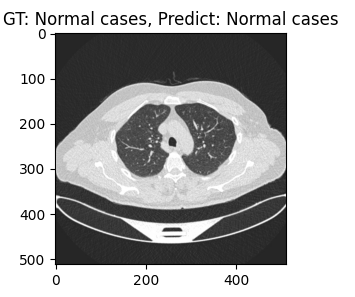

plt.figure(figsize=(3, 3))

plt.title(f'GT: {gt}, Predict: {pt}')

plt.imshow(np.array(img))

plt.show()